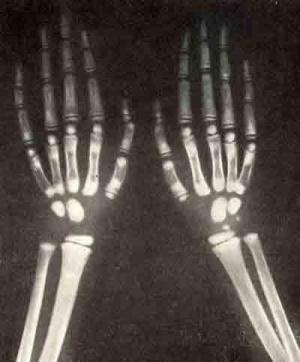

Основой диагностики мраморной болезни у детей является рентгенологическое исследование. На снимке видно, что кости имеют очень плотную структуру – они совершенно не прозрачны для рентгеновских лучей, что характерно только для этого заболевания. Кости на снимке выглядят чёрными пятнами, хотя нормальные косточки должны быть прозрачными.

Однако внешняя форма костей и их размер не изменены. Ещё один диагностический критерий – это отсутствие костномозгового канала. К тому же в некоторых случаях, но не всегда, в длинных трубчатых костях на рентгенограмме видны просветления. Это и придаёт косточкам мраморный оттенок, поэтому болезнь получила название мраморной.